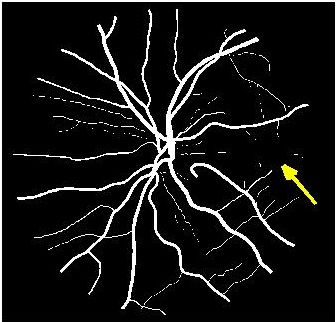

Figure 3 shows super resolution results for retinal fundus images. The image has been downsampled by a factor of each along rows and columns, and the original image is obtained using different methods. shows better reconstruction results (Fig. 3 (d) )than most competing methods. However the reconstruction is a bit blurry for small retinal vessels using as indicated by the yellow arrow. This defect is overcome using the proposed architecture (Fig. 3 (c) ), thus justifying the use of progressive GANs over saliency maps for image super resolution.

Figure 4 (a) shows an example retinal image followed by its ground truth manual segmentation in Figure 4 (b). Figure 4 (c) shows segmentation result for scaling factor when using the original HR images to train the U-Net followed by the results when trained on the super resolved images generated by , (Figure 4 (d)), (Figure 4 (e)), (Figure 4 (f)), SR-RF (Figure 4 (g)), SSR (Figure 4 (h)) and (Figure 4 (i)). Obviously the results from provide results most similar to those of HR images. This is also validated by the quantitative results in Table 3. The areas where different methods are unable to obtain accurate segmentation are highlighted by yellow arrows. Due to poor quality of super resolved images most of the methods do not segment the finer vasculature structures, while SSR and SR-RF are unable to segment some of the major arteries. Importantly, our method performs much better than the low resolution image () which performs poorly due to low resolution.

![]() |

| (a) | (b) | (c) | (d) | (e) |

| (f) | (g) | (h) | (i) | (j) |